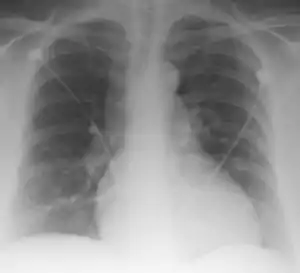

Palla's sign

Palla's sign is a clinical sign in which an enlarged right descending pulmonary artery is seen on the chest x-ray in patients with pulmonary embolism. It is of low sensitivity, and its specificity is not known. It exhibits as a "sausage" appearance on X-ray. [1] It is named after italian radiologist Antonio Palla. In 1983, he published his observations that close to 25% of patients with pulmonary embolism had a chest x-ray sign of enlarged right descending pulmonary artery.[2][3]

| Palla Sign and Westermark Sign | |